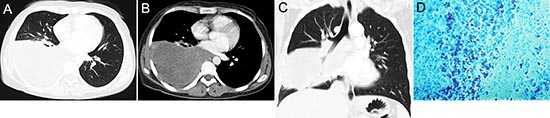

Figure 8: pPNET in a 30-year-old woman. CT imaging showed an irregular iso-dense mass in the right lower lung (A) that invaded the mediastinum (B). Coronal images using lung windows demonstrated invasion of the right lower lobe bronchus (C). The poorly differentiated small round tumor cells were CD99 positive (D × 100).